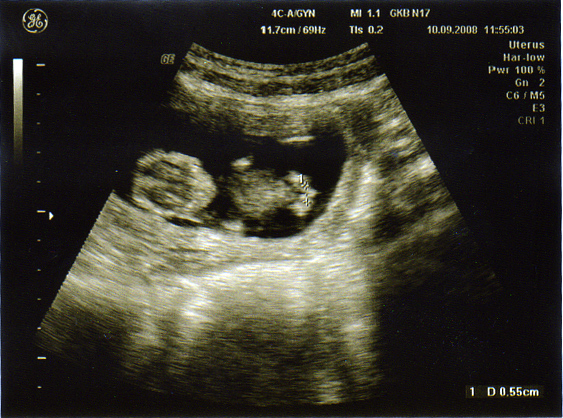

и фоточка Даша в животике 12 недель